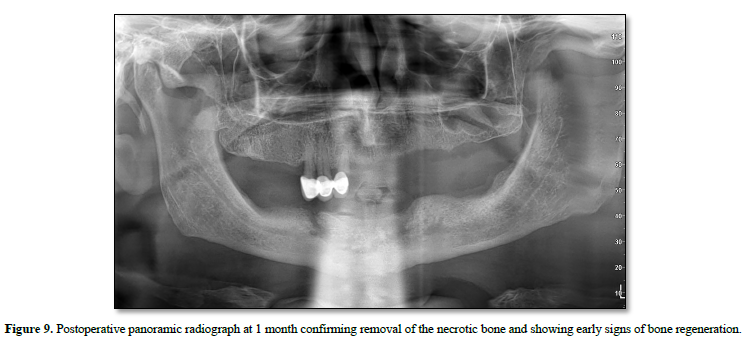

Postoperatively, the patient received systemic antibiotics, nonsteroidal anti-inflammatory drugs, a short course of corticosteroids, and chlorhexidine mouth rinses. Early postoperative follow-up demonstrated favorable soft tissue and bone healing with satisfactory clinical recovery. At the 1-month follow-up, the panoramic radiograph confirmed complete removal of the necrotic segment and showed early signs of bone regeneration (Figure 9).